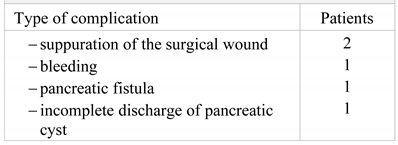

The ultrasound examination at 3 postoperative days reveals residual fluid in the cyst, for which reason the surgical re-intervention with local anesthesia by the repositioning of the drainage tubes is decided upon and performed (Figure 3).

Figure 3.

The ultrasound examination of the pancreatic pseudocyst.